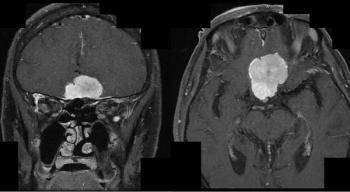

A 71-year-old woman with a past medical history of rectal cancer presents with complaints of her “eyes not working.” Physical exam is notable for incongruent bitemporal visual field defects. An MRI of the brain with gadolinium contrast was obtained. What is the diagnosis?